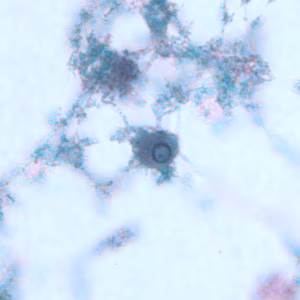

E. gingivalis trophozoites stained with trichrome.

There is no known cyst stage for Entamoeba gingivalis; trophozoites measure 10-20 µm. Trophozoites possess a single nucleus that contains a small, centrally-located karyosome and fine peripheral chromatin. The cytoplasm often contains ingested leukocytes, bacteria and other debris, very rarely red blood cells. The trophozoites may also extend agranular pseudopodia while the main cell cytoplasm remains granular in appearance. Living specimens can move quickly.